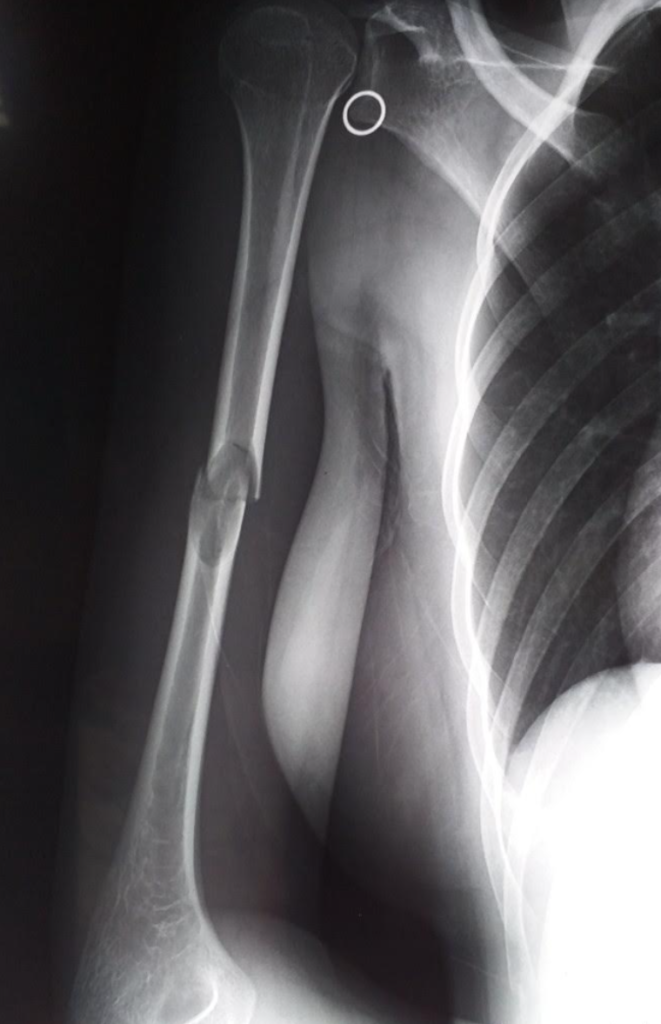

Hôm vừa rồi, nhân đi hội chẩn tại khoa ngoại chấn thương, tôi chú ý đến bệnh án của một trường hợp gãy 1/3 giữa thân xương cánh tay phải.

Đó là một cô bé 15 tuổi, vào viện 2 tuần trước sau khi bị chấn thương cánh tay phải trong khi luyện võ (cô bé là một vận động viên võ taekwondo, vừa học vừa tham gia huấn luyện thi đấu).

Khai thác bệnh sử thấy chấn thương không mạnh lắm (chỉ là đưa tay đỡ cú đá của bạn tập), nhưng em thấy đau nhiều và mất chức năng cánh tay phải. Tuy vậy em không bị chảy máu hoặc rách da vùng chấn thương. Em nhanh chóng được mọi người đưa vào viện, chụp X quang và xác định là gãy ngang 1/3 giữa thân xương cánh tay phải. Một điều bất ngờ nữa là X quang phát hiện một vùng khuyết xương kích thước bằng quả trứng cút ở vùng gãy (ban đầu bệnh án ghi là theo dõi là nang xương đơn độc).

Xương gãy được cố định tạm thời, trong khi chờ đợi kết quả xét nghiệm bổ sung (chụp CT scan xương cánh tay). Ngày hôm sau, kết quả CT vẫn theo dõi nang xương, và em đã được khoa ngoại mổ phiên sau một tuần để vừa cố định xương gãy bằng nẹp vít, vừa nạo và lấy tổ chức u/nang làm giải phẫu bệnh, vừa đốt tổ chức u bằng cồn 90 độ và lấp khoảng trống bằng ghép xương tự thân.

Đây là một trường hợp gãy kín 1/3 giữa thân xương cánh tay phải, gãy ngang, ít di lệch.

Gãy xương trong trường hợp này xảy ra sau một chấn thương ở cánh tay. Tuy nhiên, lực chấn thương rất nhẹ, khó có thể gây gãy nếu xương không bị làm yếu trước đó. Việc phát hiện u/nang xương ở đây là tình cờ, và nang/u đã chiếm gần hết đường kính (ngang) của thân xương cánh tay, làm giảm rõ độ cứng của cấu trúc xương.